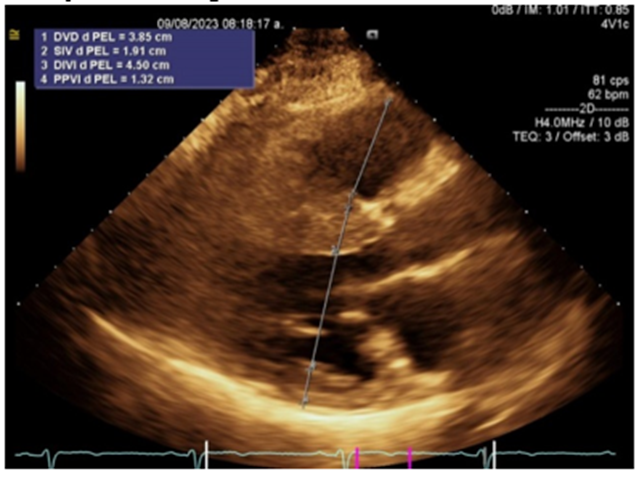

Figure 2: Long parasternal axis showing increased basal septal thickness